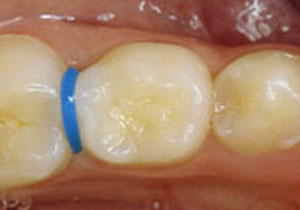

ยางแยกฟัน (Separator)

ใช้ในการเตรียมฟันเพื่อใส่เครื่องมือจัดฟันแบบติดแน่น โดยยางจะค่อย ๆ ดันฟันหลังซึ่งปกติจะอยู่ชิดกันแน่นให้หลวมขึ้น เพื่อเป็นที่อยู่ของแหวนจัดฟันหรือแบนด์ (Band)

เมื่อเริ่มใส่ยางแยกฟัน จะรู้สึกแน่น ๆ เหมือนมีเศษอาหารติด เวลากัดฟันอาจรู้สึกว่ากัดโดนยางเพราะส่วนหนึ่งของยางแยกฟันอยู่บนด้านสบฟัน ถ้ามีอาการปวดหรือแน่นมาก สามารถ ทานยาแก้ปวดได้ อาการปวดจะบรรเทาลง ใน 2-3 วัน ควรเลี่ยงอาหารเหนียวที่จะติดและดึงยางแยกฟันออก และเลี่ยงการใช้ไหมขัดฟันบริเวณนี้ชั่วคราวเพราะยางจะหลุดได้ หากยางแยกฟันหลุดเกินกว่า 3 วันก่อนวันนัดติดแบนด์ ควรติดต่อทันตแพทย์เพื่อใส่ยางให้ใหม่